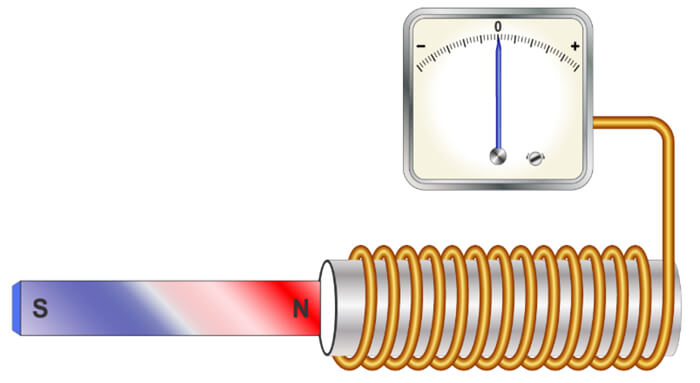

Two early 19th century discoveries ultimately led to the discovery of MRI late in the 20th century. Both of these discoveries are explained on the following slides. The experiment of Ørsted shows that a circulating current induces a magnetic field.

In 1820 after a long series of experiments, Ørsted discovered that a magnetized needle placed near a conductor moved when the wires were connected to a battery. At the time, the notions of electric circuit and current were unknown, but Ørsted suspected a link between electricity and magnetism. This experiment was the inspiration for the invention of coils to generate a magnetic field. If we turn the switch on, electrical current can flow through the coil and create a magnetic field.

In 1821, following the discovery of the phenomenon of electromagnetism by the Danish chemist Ørsted, Faraday built two machines to produce what he would call an electromagnetic rotation: the continuous circular movement of a magnetic force around a wire is the principle of an electric motor. In this experiment, if we rotate a magnetic field, shown here as a u-shaped magnet, it creates an electric current, to power a light bulb in our example.

This is still the way we generate electricity today. The magnet used is rotated as a result of the power created by the action of water such as with in hydroelectric power plants, with heat in conventional or nuclear power plants, with wind as in windmills or with mechanical effort, dynamo.

The idea of MRI came from a discovery in 1831! Michael Faraday discovered that when there was a change in magnetism within a coil of wire, a voltage resulted. When the bar magnet moves into the closed-loop, the voltage increases. When the bar magnet is removed the voltage goes down. We refer to the force created as the electromagnetic force.

Of course, Faraday had no idea that at some time in the future, we would use this technology to create electromagnetic engines, OR use the same principles to create images of the internal structures of human anatomy. The MR signal that results during an MRI examination is a small electrical current induced by the receiver coil by the precession of the net magnetization during the MR scan.

But to create this phenomenon, we must create a situation where the voltage and electromagnetic energy increases and decreases. To understand all of this, we must have a full understanding of the safety concerns surrounding these concepts.